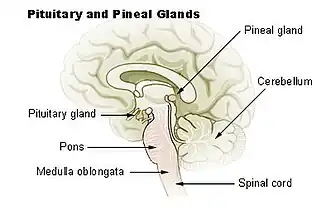

Diagrama da hipófise e glândulas pineais.

A glândula pineal, também conhecida como conarium, epífise cerebral ou simplesmente pineal, é uma pequena glândula endócrina no cérebro dos vertebrados. A glândula pineal produz melatonina, um hormônio derivado da serotonina que modula os padrões de sono nos ciclos circadianos e sazonais. A forma da glândula se assemelha a uma pinha, daí o seu nome. A glândula pineal está localizada no epitálamo, perto do centro do cérebro, entre os dois hemisférios, escondida em um sulco onde as duas metades do tálamo se unem.[1][2]

A glândula pineal é uma estrutura cinza-avermelhada do tamanho aproximado de caroço de uma laranja, com massa aproximada de 150 mg (medindo em média 5 por 8 mm em humanos),[8] localizada logo superiormente ao colículo superior e atrás da stria medullaris, entre os corpos talâmicos posicionados lateralmente. Anatomicamente, é considerada parte do epitálamo. É uma estrutura epitalâmica pequena e única, situada dorsalmente à região caudal do diencéfalo. Ela é derivada de células neuroectodérmicas e, à semelhança da retina, desenvolve-se a partir de uma invaginação do teto da parede do terceiro ventrículo.[carece de fontes]